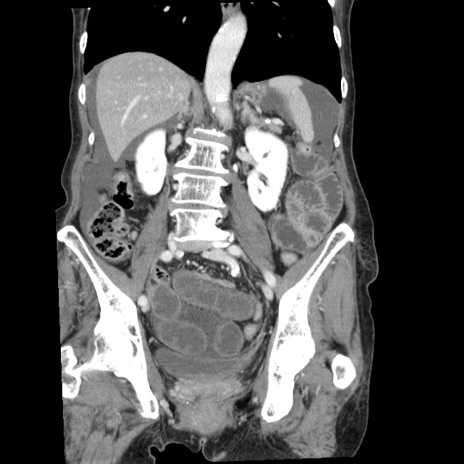

症例1(冠状断像)

【症例】80歳代女性

【主訴】腹痛

【現病歴】8時間前から腹痛あり来院。

【既往歴】糖尿病、脂質異常症、子宮体癌にて子宮全摘術

【身体所見】意識清明・会話良好だが腹痛で苦悶様、全腹部にわたって反跳痛と圧痛あり

【データ】WBC 13600、CRP 0.14、LDH 224、CK 90